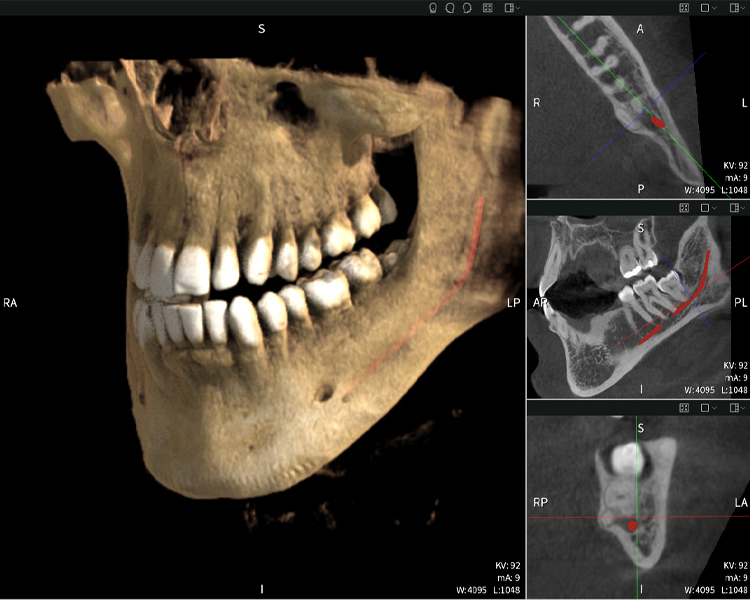

Below you will find a case from Dr. med. dent. Oliver A. Centrella, in which the CBCT images obtained with Seethrough Max provided crucial information on the complex anatomy and the critical relationship between the wisdom teeth and the inferior alveolar nerve. In this case, there is a indication for the surgical removal of the wisdom teeth.

Figure a: Imaging results of Seethrough Max, in front of a black background.

Figure a

• Top left: Axial cross-section of the left mandible (region 38) showing the inferior alveolar nerve (red) in proximity to the roots of tooth 38.

• Top right: 3D reconstruction of the entire mandible for orientation. The red-marked inferior alveolar nerve illustrates its location within the jawbone.

• Bottom left: Sagittal view of the mandible (region 38), highlighting the close spatial relationship between the roots and the nerve canal.

• Bottom right: Coronal view of the mandible (region 38), which is crucial for assessing the spatial position of the roots relative to the nerve.